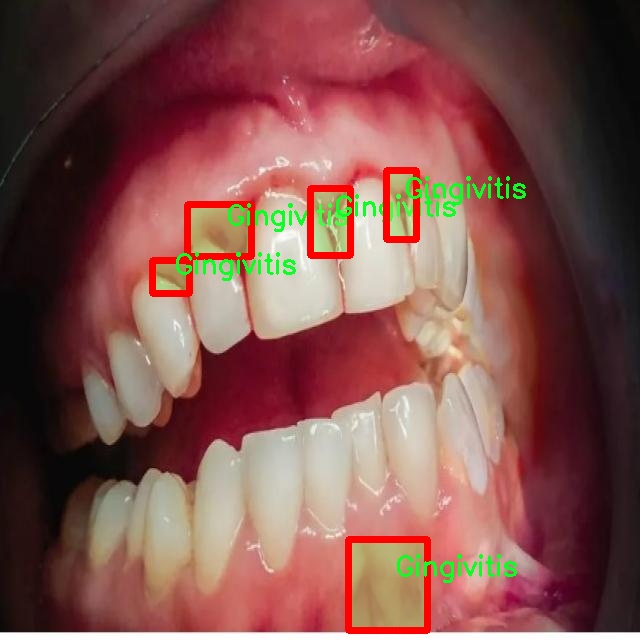

图片效果

在本研究中,我们使用了名为“unbeknownst to man”的数据集,旨在改进YOLOv8-seg的口腔疾病图像分割系统。该数据集专注于口腔健康领域,涵盖了四种主要的口腔疾病类别,分别是龋齿(Caries)、牙龈炎(Gingivitis)、牙齿变色(Tooth Discoloration)和溃疡(Ulcer)。这些类别的选择不仅反映了口腔疾病的多样性,也为我们提供了一个全面的视角,以便更好地理解和分析这些疾病的表现形式及其在图像中的特征。

数据集中的每个类别都包含大量高质量的图像,这些图像经过精心标注,确保了每个样本的准确性和一致性。龋齿作为最常见的口腔疾病之一,其图像展示了不同阶段的龋齿发展,从初期的微小白斑到严重的牙体损坏,图像中清晰的细节为模型训练提供了丰富的信息。牙龈炎则通过展示红肿、出血等症状,帮助模型学习如何识别和分割出受影响的牙龈区域。牙齿变色的图像则展示了因多种因素导致的牙齿色泽变化,这些变化可能是由于饮食、生活习惯或口腔卫生不良等原因引起的。最后,溃疡的图像则提供了对口腔内病变的直观表现,通常伴随着疼痛和不适,这类图像的标注对于识别和分割至关重要。